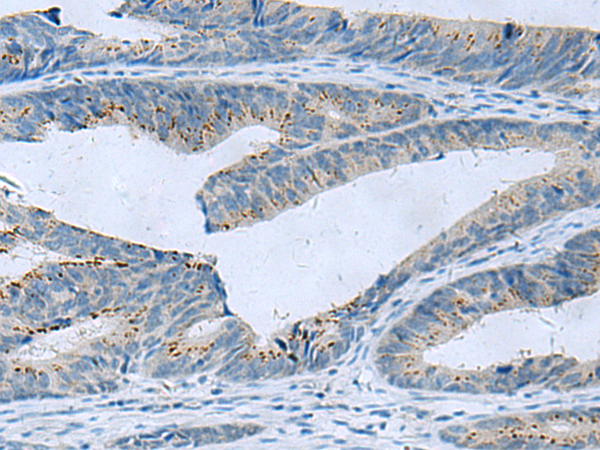

ELISA, IHC |

IHC positive control: |

Human liver cancer and Human colorectal cancer |

IHC Recommend dilution: |

50-100 |